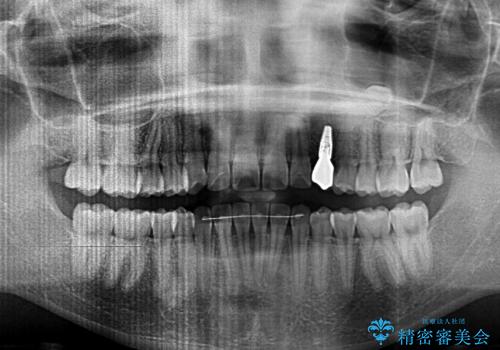

また、インプラント治療については、インビザラインによる矯正治療中の最適なタイミングで治療を行い、治療期間の短縮を図ることとしました。

インプラントは、治療期間を短くすることが可能な、ストローマン社のSLActiveを使用することとしました。

インプラント治療は当初の狙い通り、矯正治療期間中に行い、スムーズに処置を進めることができました。

歯並びが整ったことで治療前に認められた歯肉炎は全くなくなり、患者様には大変満足していただきました。